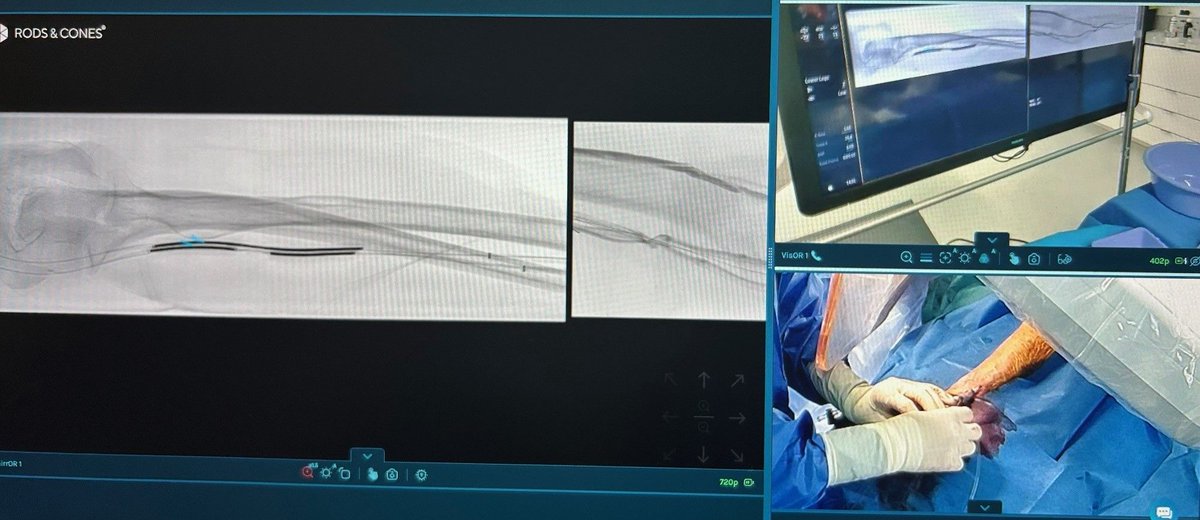

Scrub into the OR remotely and in real-time with Rods&Cones! 🚀

Connect medical experts worldwide. 🌍